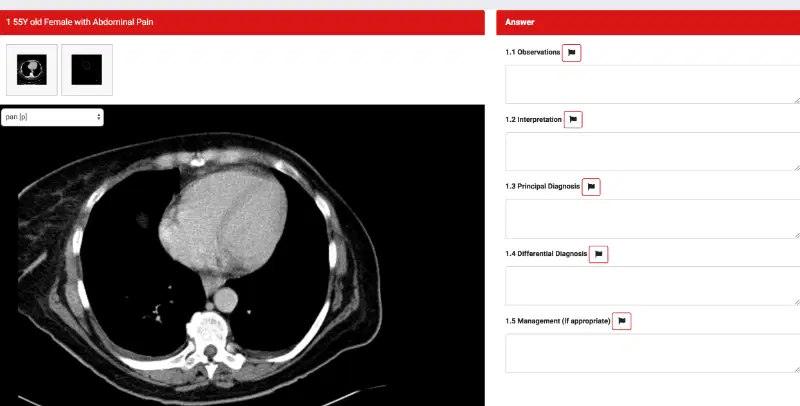

2. Reporting Session (FRCR 2B long cases)

You get six cases and have the opportunity to attain a maximum of 8 marks for each case, so a maximum of 48 marks. Total time allotted is 55minutes for ALL the cases.

Marking system for individual cases. is as follows:

| Candidate response | Mark |

|---|---|

| No answer offered | 3 |

| Fail: significant observations missed; correct diagnosis not made | 4 |

| Borderline: appropriate if there are two main diagnoses in the case but only one is mentioned; some observations missed | 5 |

| Pass: most observations made correctly; principal diagnoses correct | 6 |

| Good Pass: additional relevant material included in a “pass” grade answer | 7 |

| Excellent: a perfect answer, clear and confident | 8 |

Depending on the total for each case, the candidate is awarded a total score out of 8 as follows:

| Total marks | Overall mark |

|---|---|

| 18-25 | 4 |

| 25½-28 | 4½ |

| 28½-31 | 5 |

| 31½-34 | 5½ |

| 34½-37 | 6 |

| 37½-40 | 6½ |

| 40½-43 | 7 |

| 43½-46 | 7½ |

| 46½-48 | 8 |